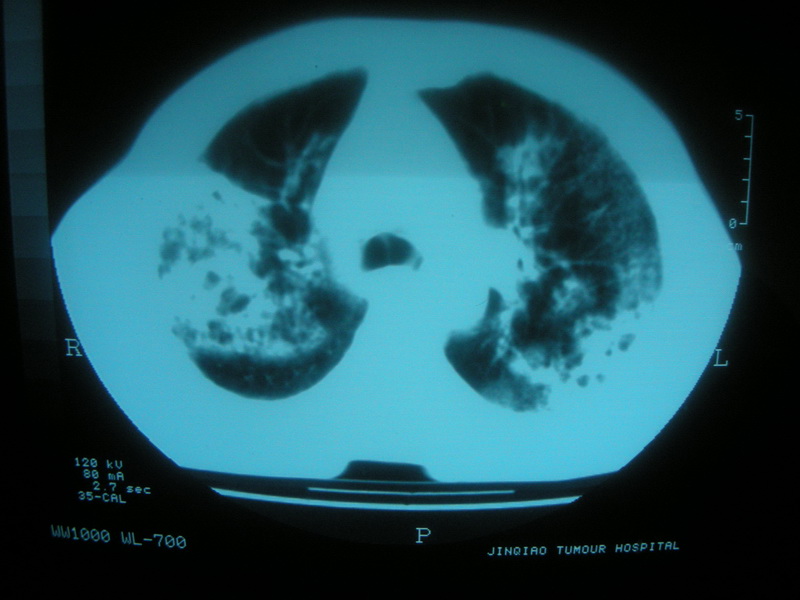

标题: CT11692:男,63岁,糖尿病史15年.抗炎治疗7天,病情 [打印本页]

标题: CT11692:男,63岁,糖尿病史15年.抗炎治疗7天,病情

请老师看看是结核还是炎症?

双肺继发性肺结核伴感染!

双肺继发性肺结核伴支气管播散。

考虑双肺继发性肺结核。合并炎症。